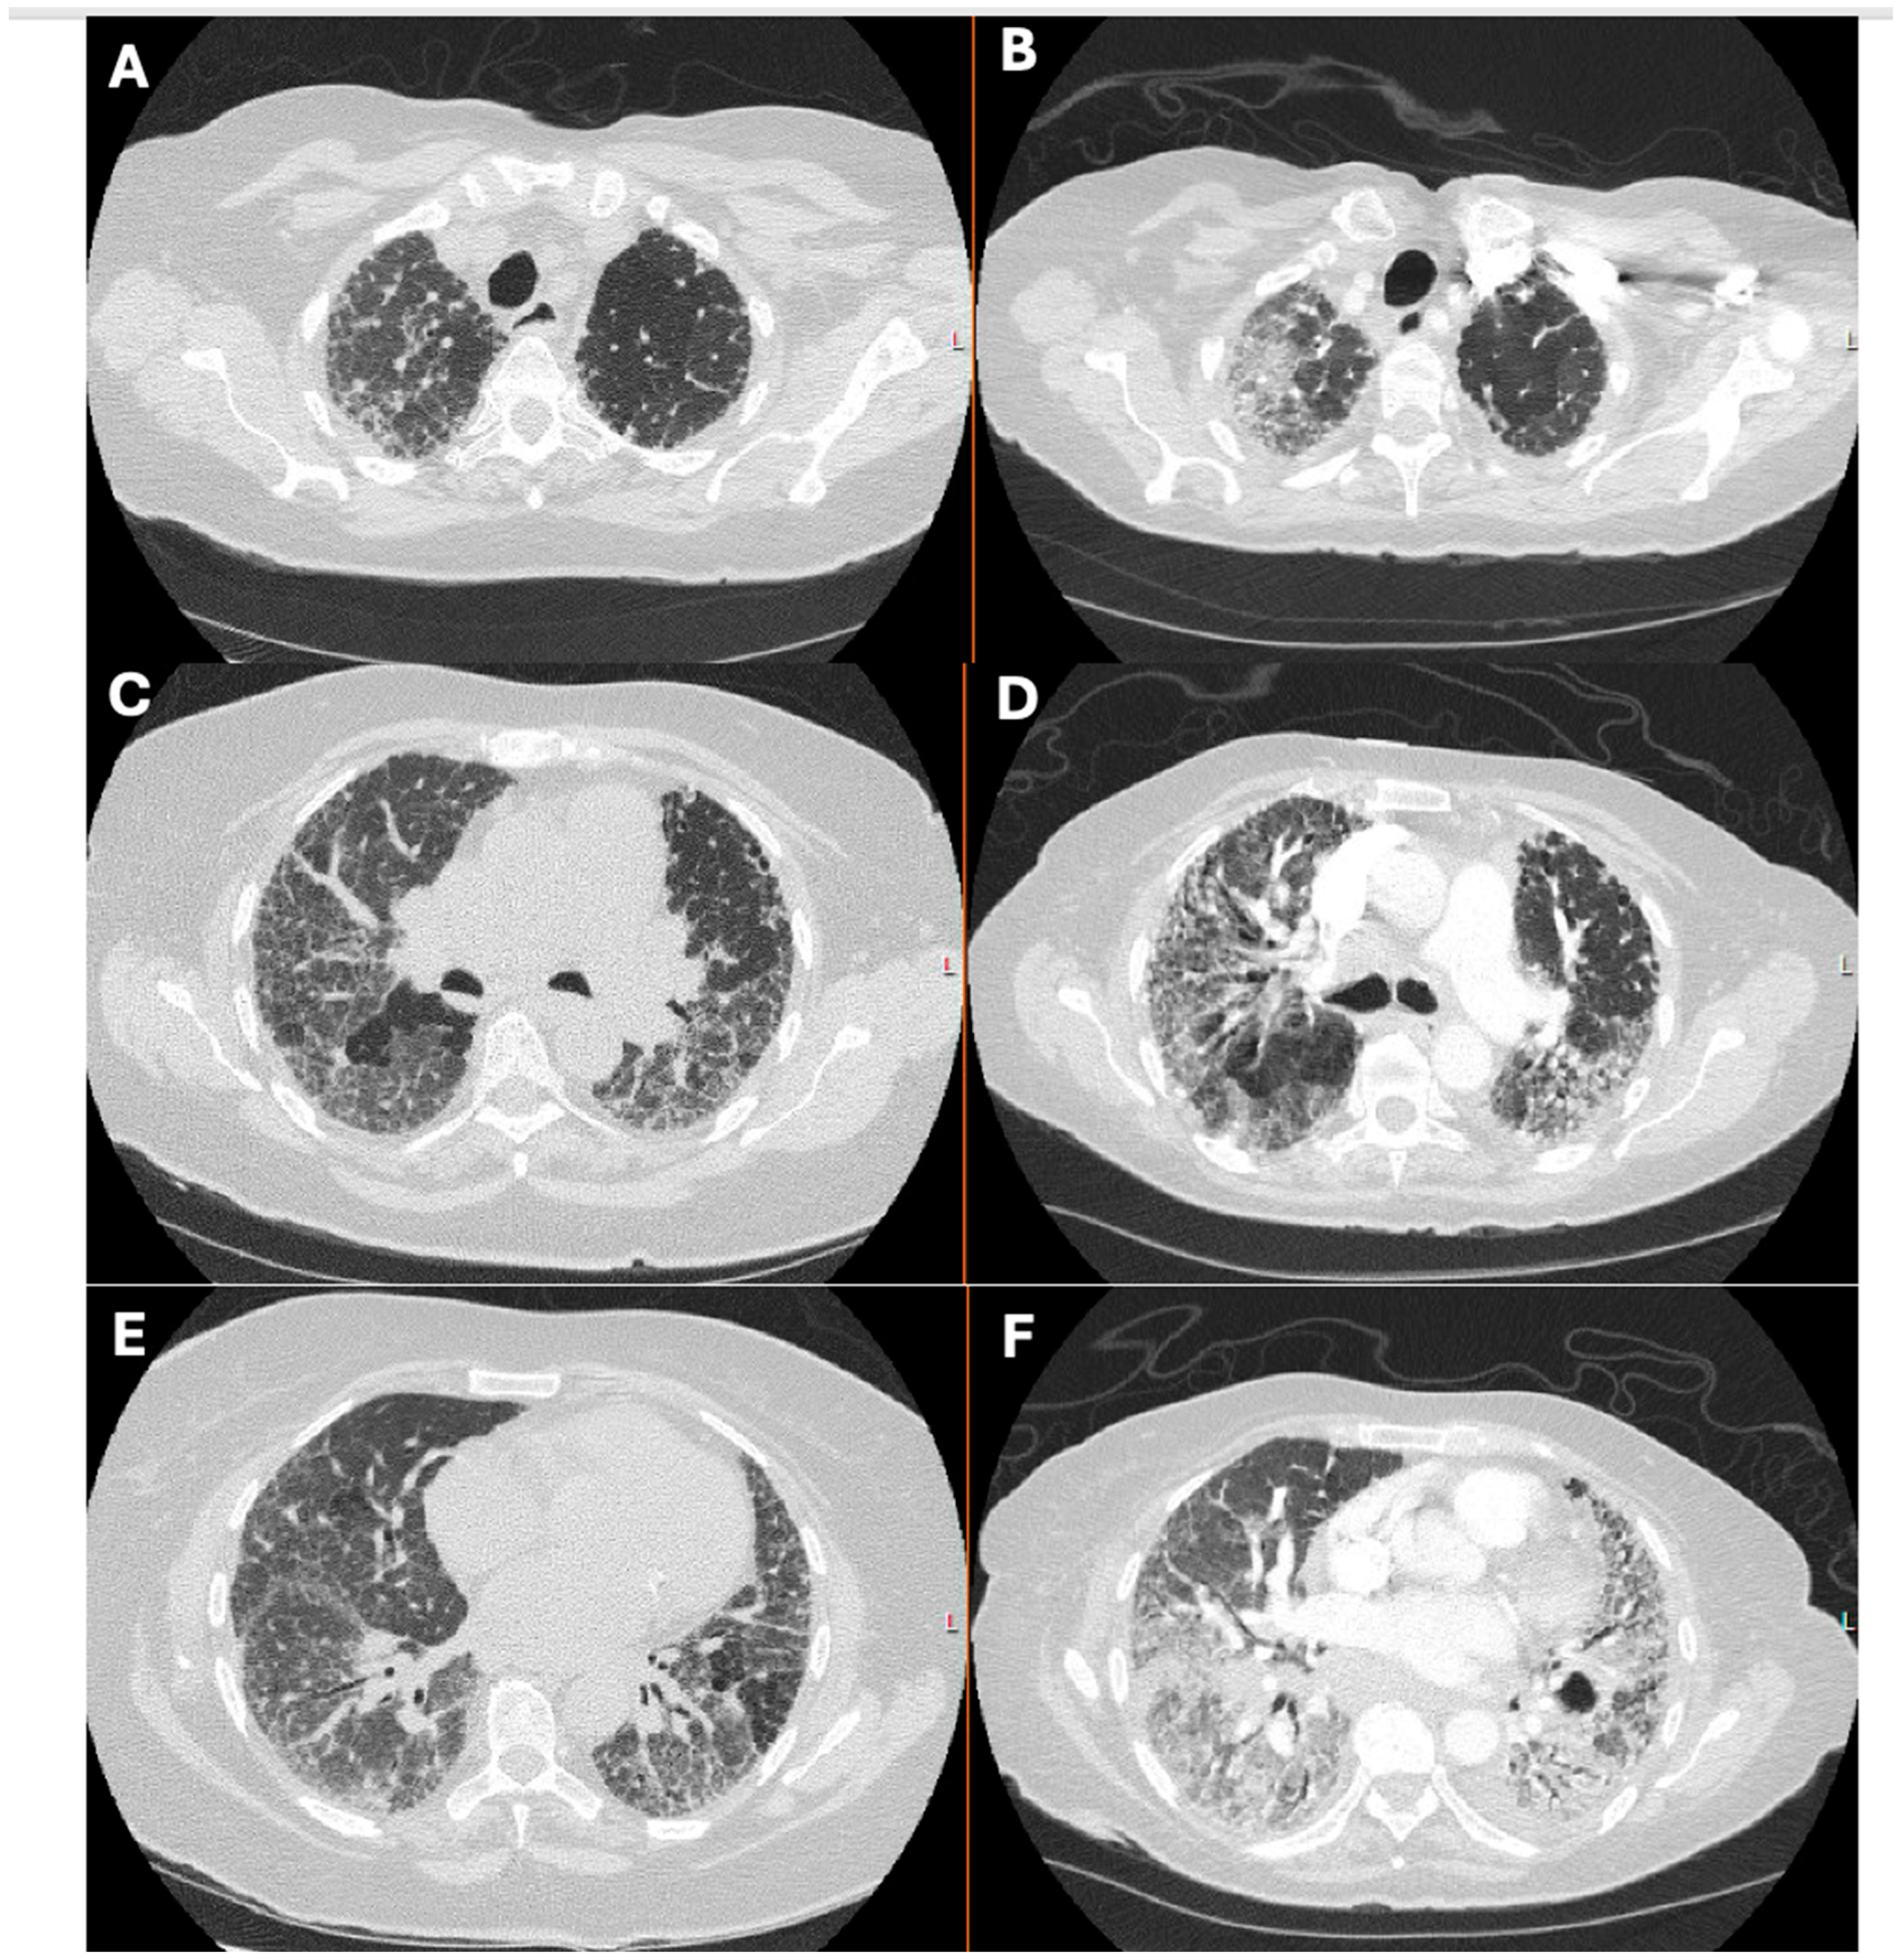

1.1. The Diagnosis and Evaluation of Patients with ILD in the ICU

- Charokopos, A.; Moua, T.; Ryu, J.H.; Smischney, N.J. Acute exacerbation of interstitial lung disease in the intensive care unit. World J. Crit. Care Med. 2022, 11, 22–32. [Google Scholar] [CrossRef]

- Suzuki, A.; Kondoh, Y.; Brown, K.K.; Johkoh, T.; Kataoka, K.; Fukuoka, J.; Kimura, T.; Matsuda, T.; Yokoyama, T.; Fukihara, J.; et al. Acute exacerbations of fibrotic interstitial lung diseases. Respirology 2020, 25, 525–534. [Google Scholar] [CrossRef]

- Alhamad, E.H.; Cal, J.G.; Alrajhi, N.N.; AlBoukai, A.A. Acute exacerbation in interstitial lung disease. Ann. Thorac. Med. 2021, 16, 178–187. [Google Scholar] [CrossRef]

- Miller, W.T.; Shah, R.M. Isolated Diffuse Ground-Glass Opacity in Thoracic CT: Causes and Clinical Presentations. Am. J. Roentgenol. 2005, 184, 613–622. [Google Scholar] [CrossRef] [PubMed]